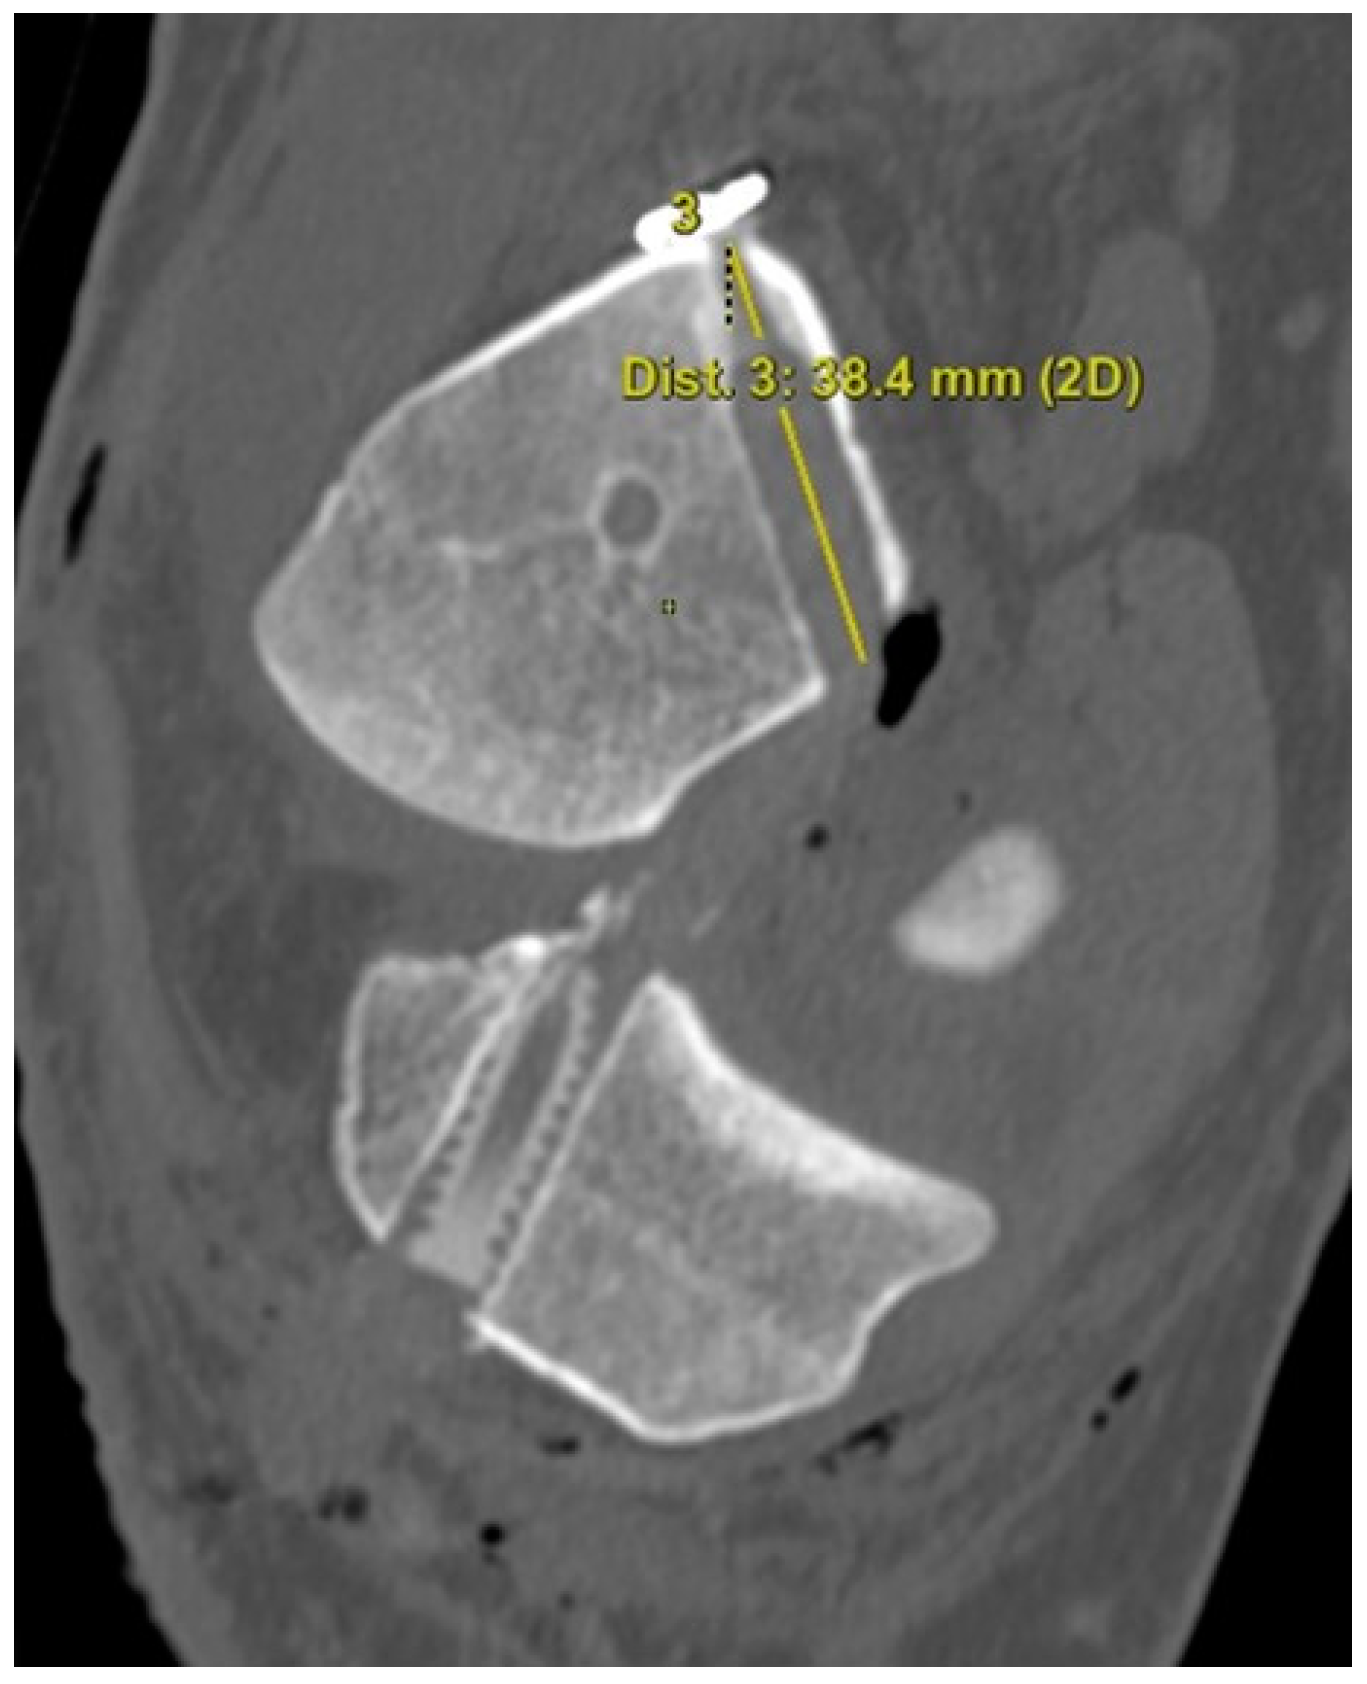

The 3D CT scans were imported into 3D software (AW Sever 3.2 PACS system, GE Healthcare; Chicago, IL, USA) for the assessments of the femoral graft bending angle and femoral tunnel length. The femoral graft bending angle was defined as the angle formed by the longitudinal axis of the femoral tunnel and the line connecting the intra-articular aperture of the tibial tunnel and the intra-articular aperture of the femoral tunnel (Figure 3). The femoral tunnel length was defined as the distance between the center of the extra-articular aperture of the femoral tunnel and the center of the intra-articular aperture of the femoral tunnel in a plane where the entire femoral tunnel could be viewed (Figure 4). Posterior wall breakage of the femoral tunnel was also checked.

Figure 4.

The femoral tunnel length is defined as the distance between the center of the extra-articular aperture of the femoral tunnel and the center of the intra-articular aperture of the femoral tunnel.

Regarding the femoral tunnel location, it was located at 29.7 ± 4.4% in the posterior to anterior (deep to shallow) direction and at 24.1 ± 5.9% in the proximal to distal (high to low) direction. The mean femoral graft bending angle was 113.9 ± 5.7°, and the mean femoral tunnel length was 35.2 ± 3.1 mm (Table 3). There were no cases of a femoral tunnel length <30 mm because the guide pin was redirected for those <30 mm while making the knee joint flexion to approximately 110°. Posterior wall breakage was observed in five patients (8.3%). In the MRIs, the mean coronal graft inclination was 69.2 ± 4.7°, and the mean sagittal graft inclination was 52.4 ± 4.6° (Table 3). The mean posterior tibial slope 241 was 7.9 ± 3.5, and there was no posterior tibial slope of more than 12°.